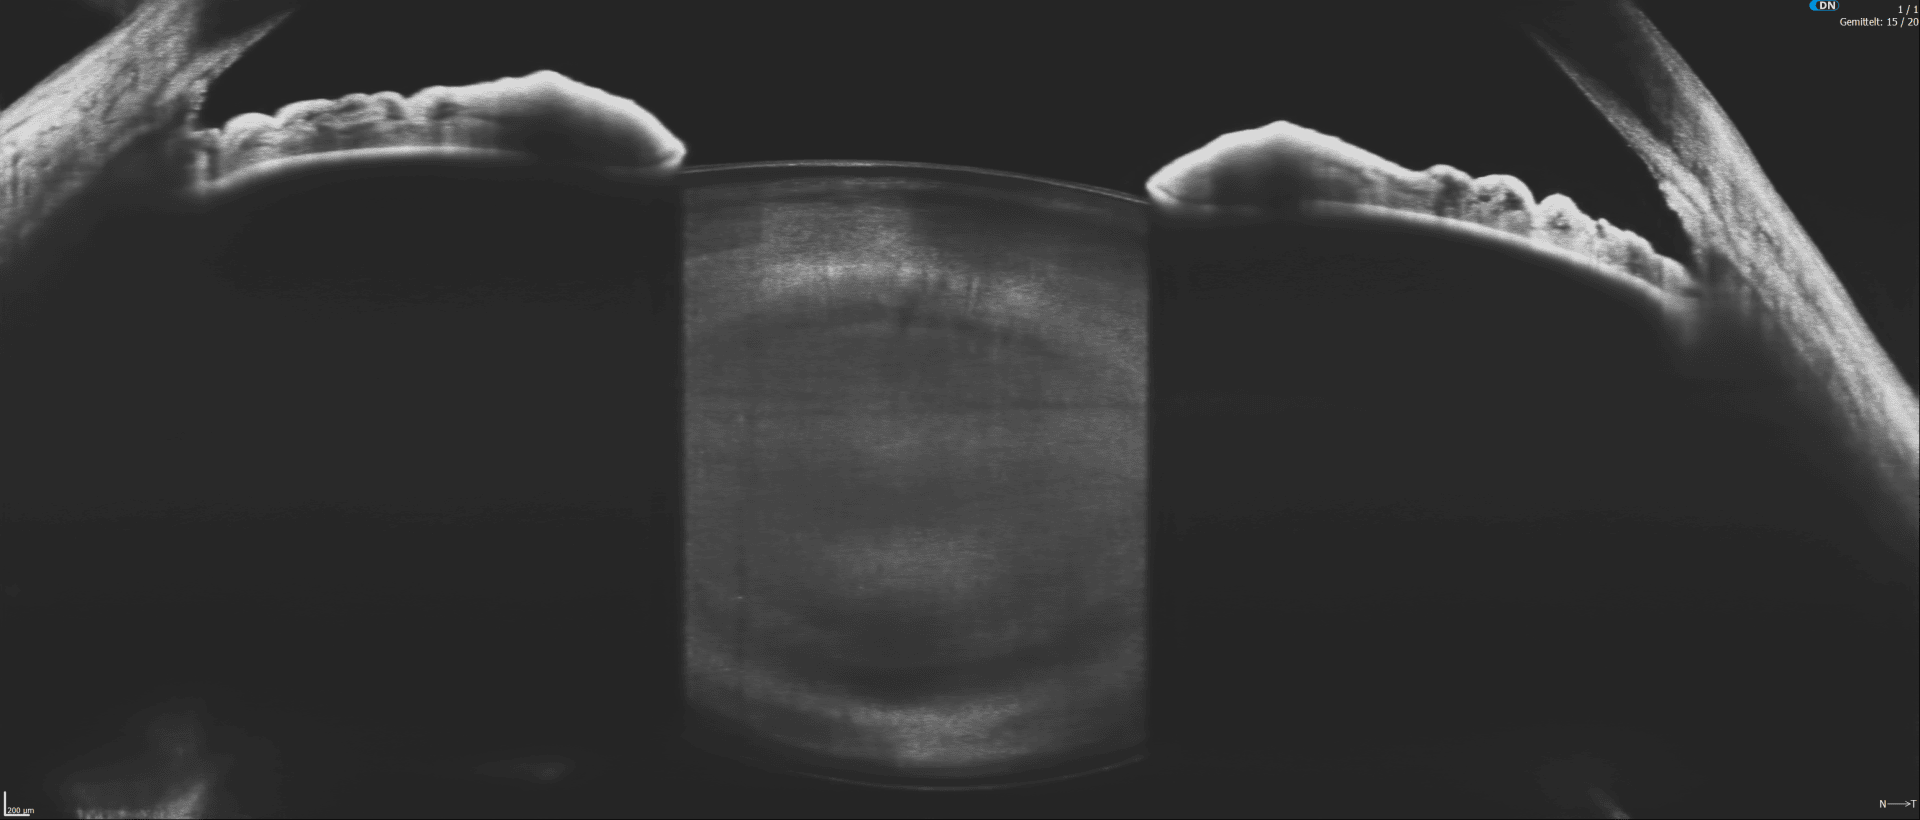

Alle Modelle überzeugen durch ihre Vollausstattung: Netzhaut-Screening, Glaukom-Analyse, Vorderabschnitt-Scans, Gonioskopie und Pachymetrie - alles vollautomatisch und gestützt durch eine normative Datenbank zur unabhängigen Befundbewertung. Optional erweitern Funktionen wie Biometrie, Hornhauttopographie und OCT-Angiographie die Einsatzmöglichkeiten.